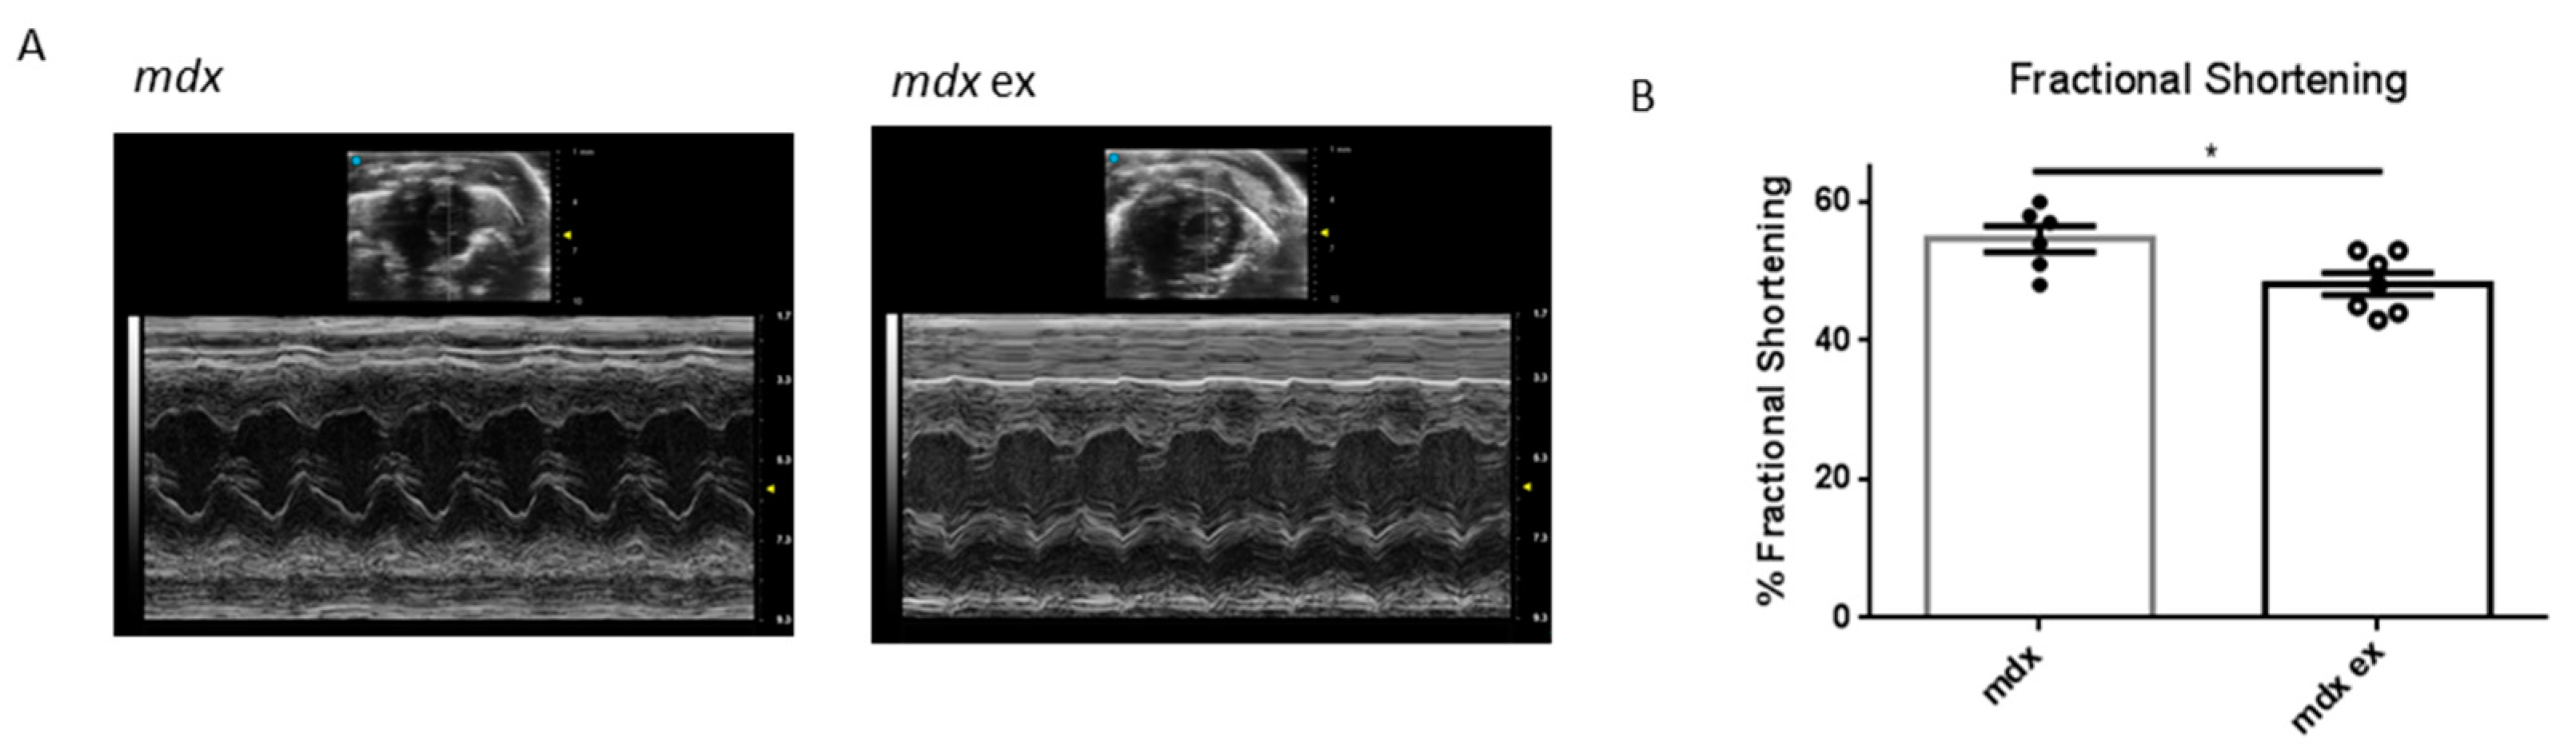

3.5. The Exercise Protocol Alters Mdx Heart Function

mdx | 2.77 ± 0.07 | 1.27 ± 0.08 | 1.13 ± 0.04 | 1.08 ± 0.02 | * 54.42 ± 1.89 | 452 ± 25.2 | 7.0 ± 0.24 |

mdx ex | 2.76 ± 0.06 | 1.44 ± 0.03 | 1.06 ± 0.04 | 1.11 ± 0.03 | * 48.14 ± 1.61 | 443 ± 43.8 | 6.8 ± 0.17 |